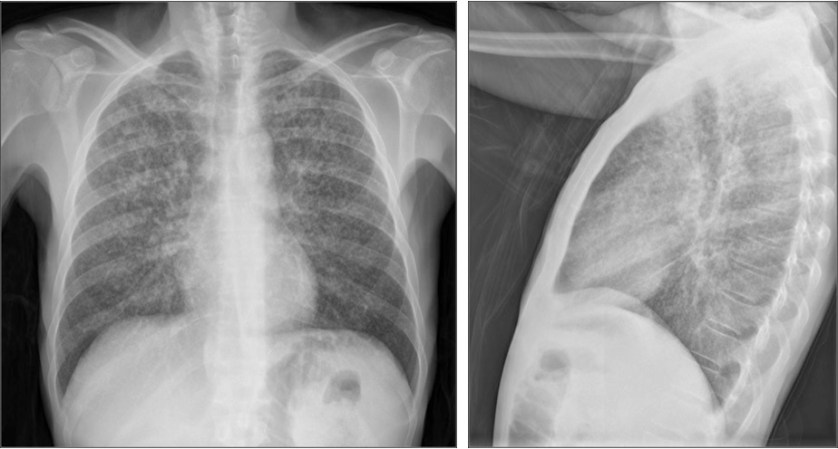

CASO: Operada de esofaguectomia y reconstrucción con coloplastia hace 3 meses. Sintomas de neumonía.

Hallazgos:

- De inicio llama la atención una densidad practicamente total del todo el hemitórax izquierdo, lo cual podría hacernos pensar que estamos ante una posible neumonía.

- Sin embargo el tórax está no está bien centrado, observar como la clavícula izquierda se encuentra casi en la mitad del pulmón, por tanto lo que vemos blanco es el mediastino ya que el tórax está rotado.

CENTRAJE:

El correcto centraje se determina comprobando que las extremidades internas de ambas clavículas equidistan de las apófisis espinosas vertebrales.

Mismo paciente, al cual esta vez se le ha tomado una radiografía en PA y en sedestación. Observar como las clavículas están equidistantes a las apófisis espinosas y como ha desaparecido el velamiento del pulmón izquierdo.

Por otra parte, paciente presenta una cardiomegalia y un discreto ensanchamiento del mediastino es probable relación con cambios postquirúrgicos.